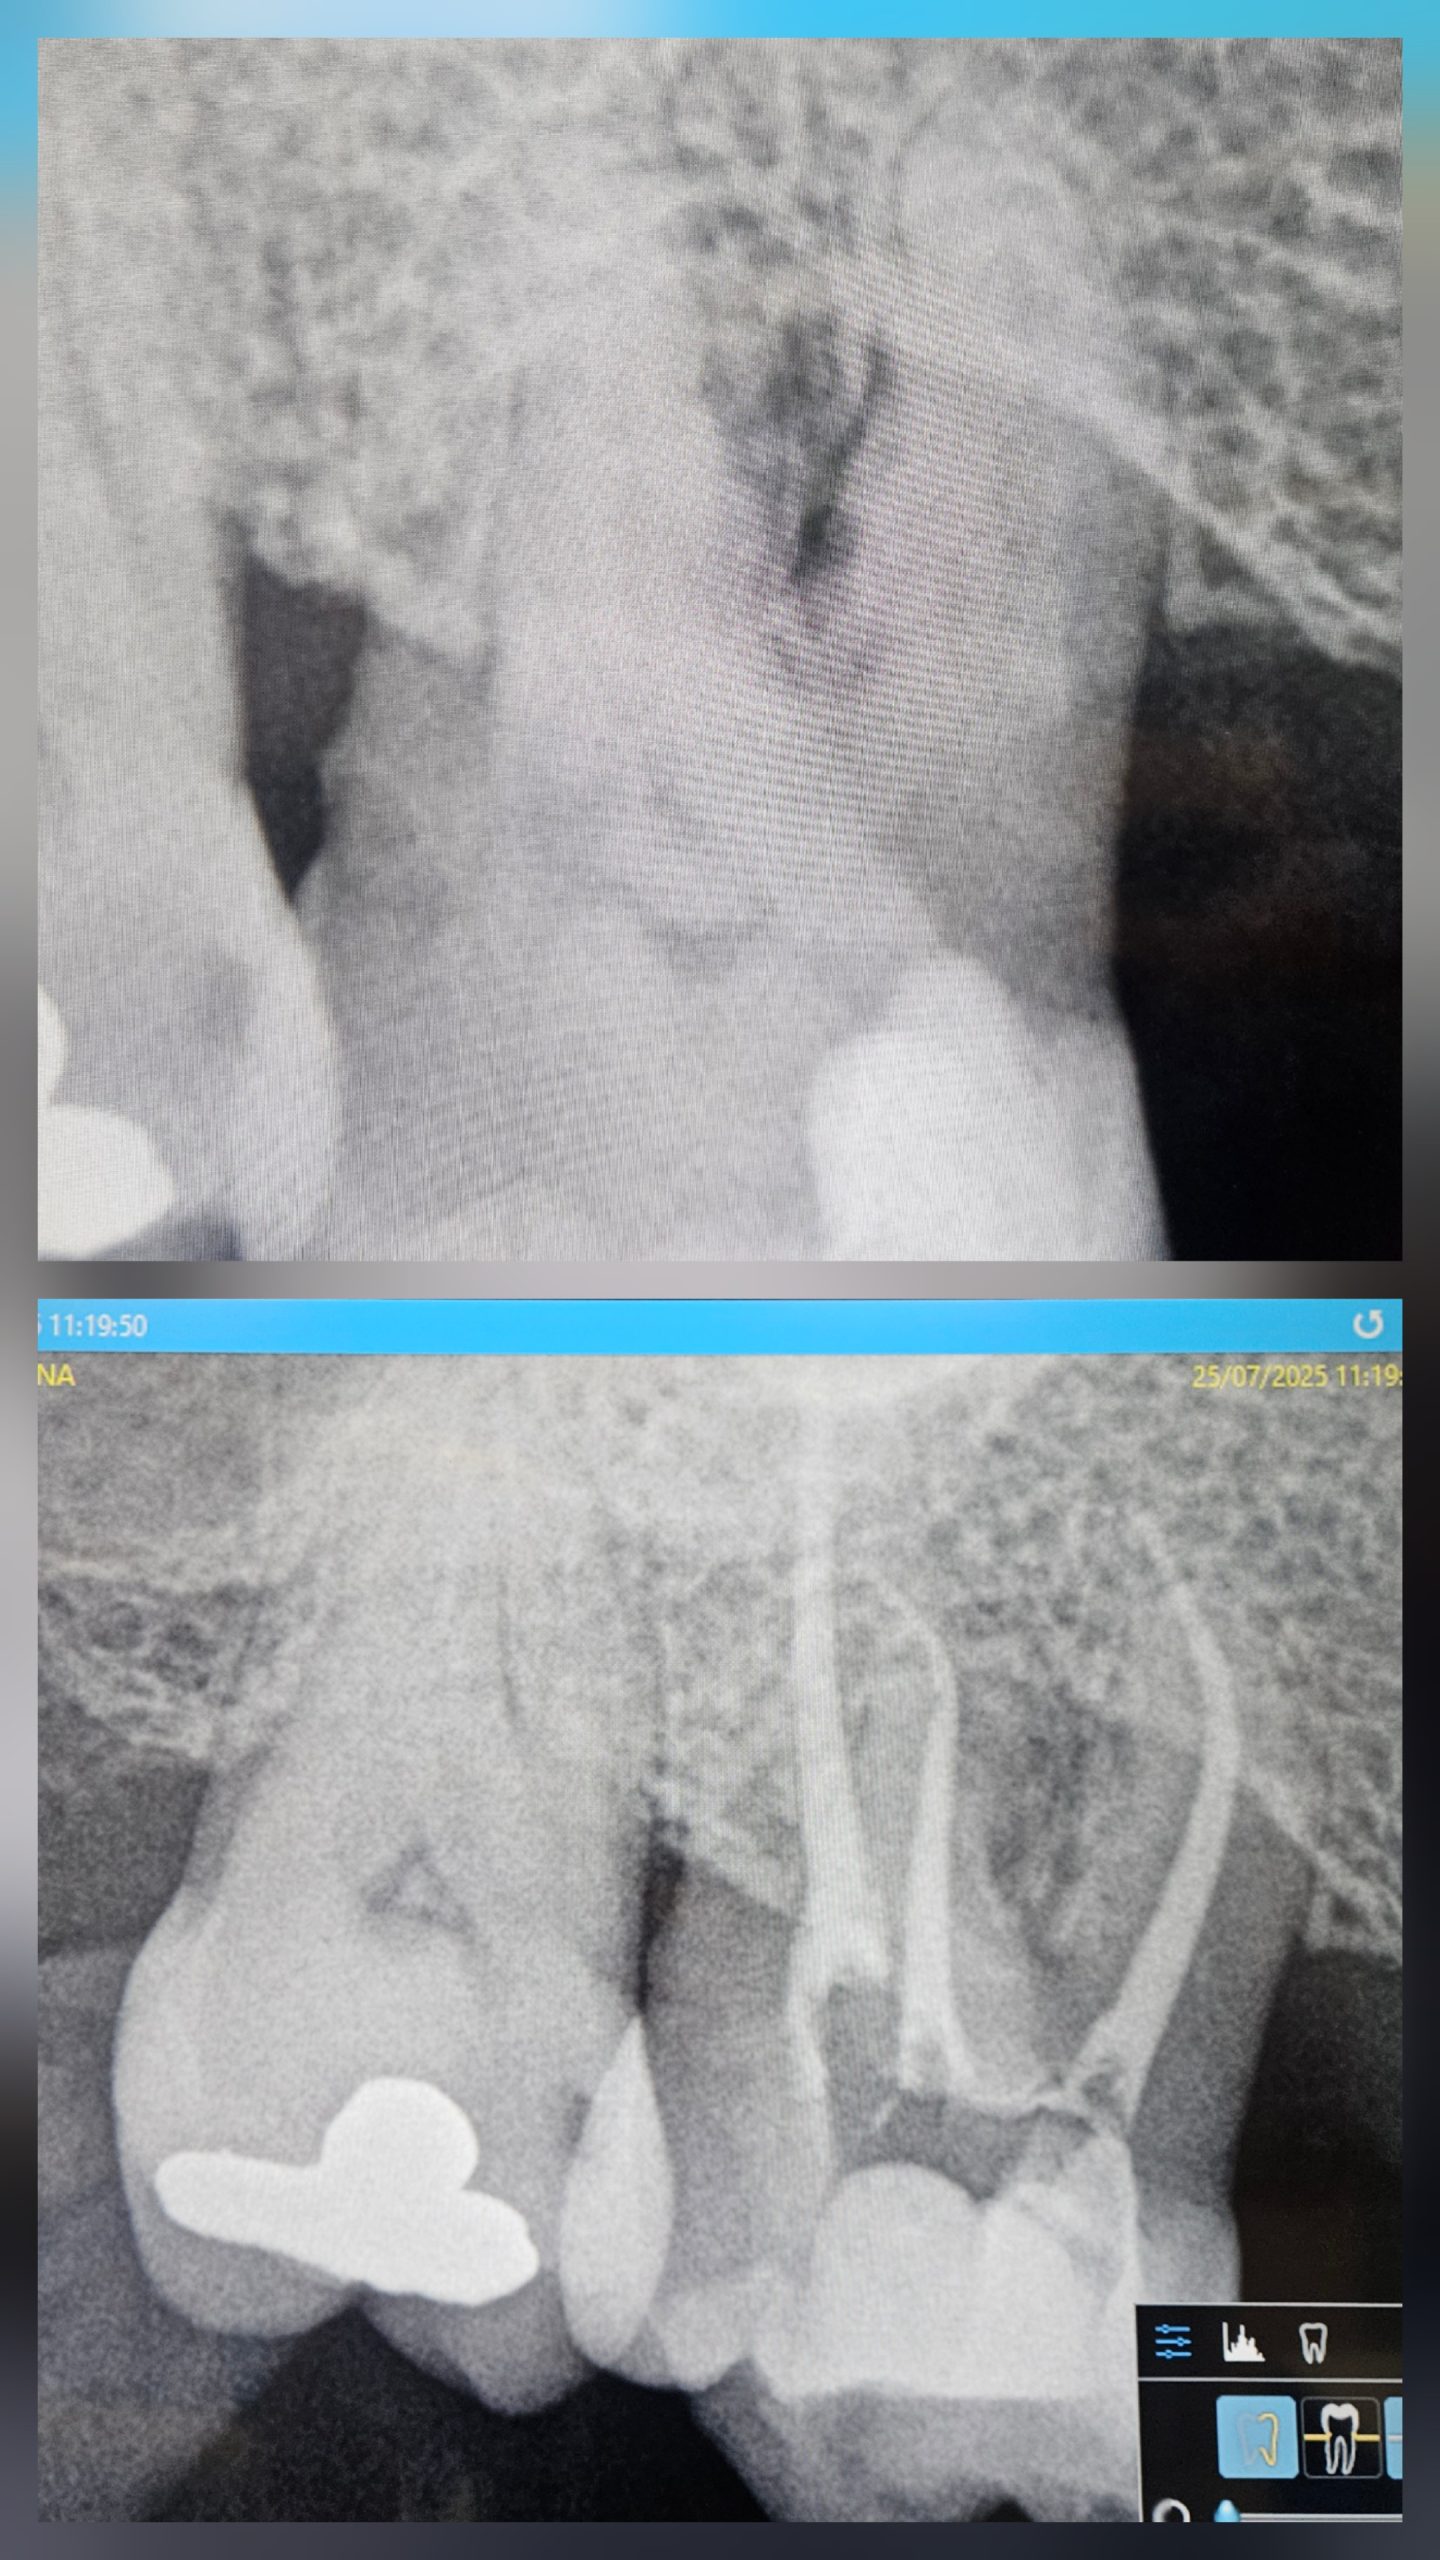

Elemento 16 estruso

Elemento 16, aperta camera e sagomato il canale con Zarc protaper fino a 30.06. Attivato Ipoclorito NaOcl al 5,75% con tecnica a caldo, alternato con Edta al 17% Si chiude con Bioceramico Guttaflow e cono master.